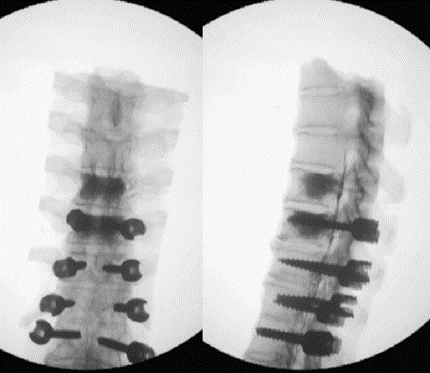

图7 术前-术后1个月-术后1个月外观